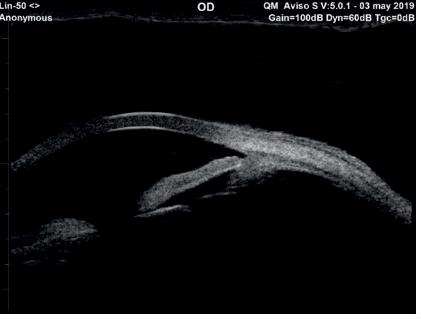

Figura 1 : Determinación por medio del UBM del mecanismo facomórfico utilizando la medida del Vault del lente. En este caso luego de trazar la línea espolón escleral espolón escleral (en verde) se tienden dos líneas perpendiculares una al endotelio (Azul) y otra a la cápsula anterior del cristalino(vault del lente, Amarilla) si la línea a la cápsula anterior (Vault del lente) es igual o mayor a un tercio de la línea al endotelio corneal el cristalino está contribuyendo fuertemente al cierre angular por causa de un mecanismo facomórfico.

El glaucoma por cierre angular es una afección “biométrica”, definida y estudiada por Lowe en 1969 (5) basándose en la medida de la longitud axial, su relación con la cámara anterior y el cristalino, pero hasta hoy ha sido poco comprendida. Actualmente por medio de la biometría óptica o ultrasónica, además de nuevas técnicas como el OCT del segmento anterior o mejor aún el UBM podemos obtener estos datos y reconocer los valores límite de riesgo de cierre angular: una cámara estrecha de menos de 2.5 mm (medida desde el endotelio hasta la cápsula anterior) junto a un cristalino mayor de 4.5 mm de grosor central, además de un adelantamiento del diafragma irido-cristaliniano, tomando como referencia la línea espolón escleral espolón escleral, definen con mucha certeza la existencia de un mecanismo facomórfico, que pone en alto riesgo la visión del paciente.(6) En múltiples oportunidades hemos sugerido a los fabricantes de equipos biométricos agregar un mensaje de advertencia cuando se obtengan estas mediciones críticas, sin ninguna respuesta efectiva hasta la actualidad.

Basados en la experiencia del UBM y OCT definimos que el riesgo de cierre angular debido al mecanismo facomórfico está presente cuando “trazamos una línea que inicia y termina en el espolón escleral visible a ambos lados de la cámara anterior, luego desde esta base tendemos otras dos líneas perpendiculares, una a la cápsula del cristalino (vault, abovedamiento o anteriorización del cristalino) y otra al endotelio corneal. Luego comparamos las medidas de ambas y las correlacionamos; si el vault del cristalino obtenido es igual o mayor a un tercio de la línea tendida hacia el endotelio podremos concluir la presencia de este mecanismo” Figura 1.

Figura 2 Características preoperatorias del mecanismo facomórfico en un paciente hipermétrope con iris Plateau asociado, con cierre angular: Se aprecia claramente que el cristalino desplaza anteriormente el diafragma iridiano cerrando el ángulo, además de so constata el incremento del Vault en relación a la línea al endotelio al lado derecho se constata la aposición del iris con el trabéculo, en ese momento no se observa goniosinequias.

Figura 3 Características postoperatorias de la resolución del mecanismo facomórfico y la persistencia de la configuración de Iris Plateau en un paciente hipermétrope. Comparando al mismo paciente casi un año después de la cirugía de lensectomía (cristalino no cataratoso) se observa la ampliación de la cámara anterior y aunque persiste la configuración anatómica de Iris plateau, el ángulo está abierto. Se puede ver claramente el espolón escleral y 500 micras delante de él, al trabéculo el cual no está expuesto a la aposición del iris, tal como se veía en el pre operatorio. La cirugía además pudo corregir el defecto refractivo con la colocación de un lente multifocal en una paciente de 43 años.